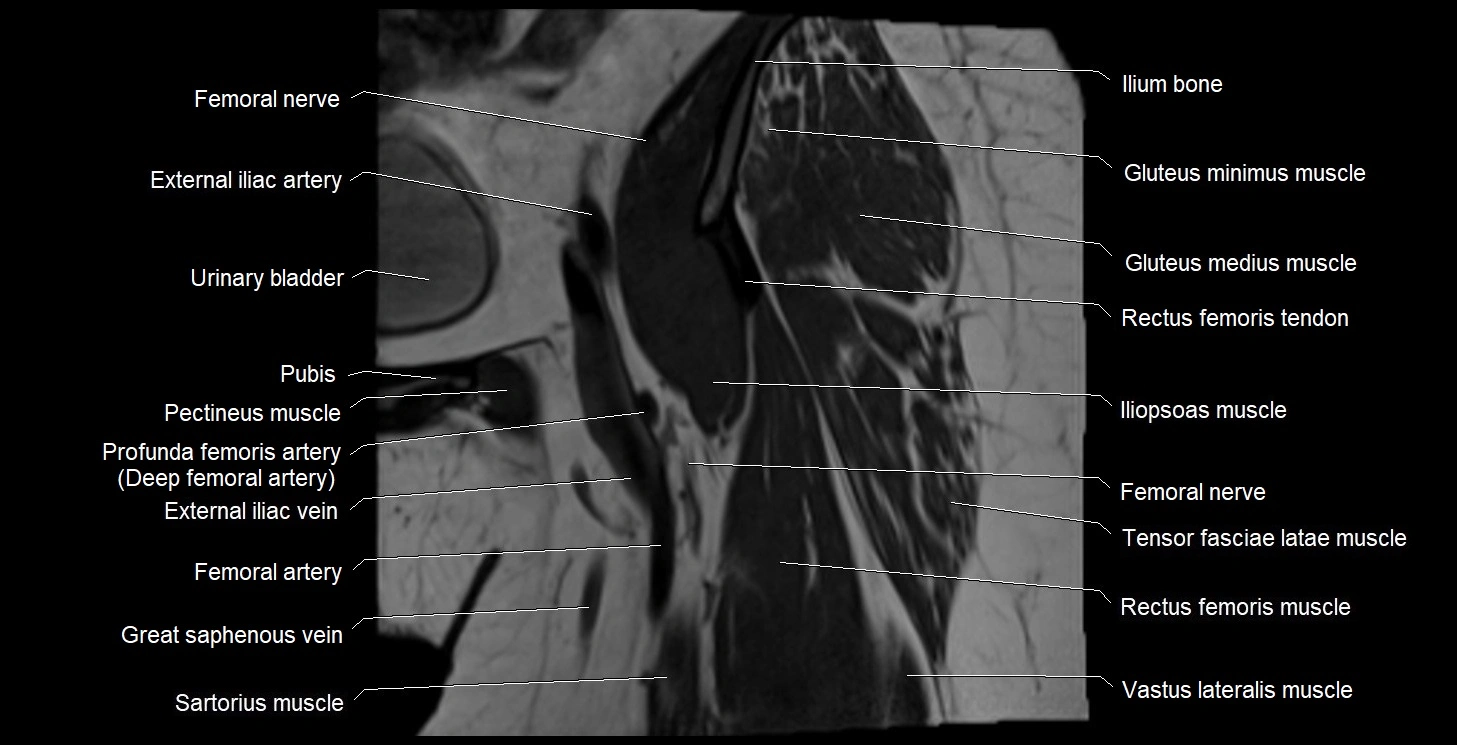

- External iliac artery

- External iliac vein

- Femoral nerve

- Gluteus minimus muscle

- Iliopsoas muscle

- Ilium bone

- Pectineus muscle

- Rectus femoris muscle

- Rectus femoris tendon (Proximal tendon of rectus femoris)

- Tensor fasciae latae muscle

- Urinary bladder

- Vastus lateralis muscle